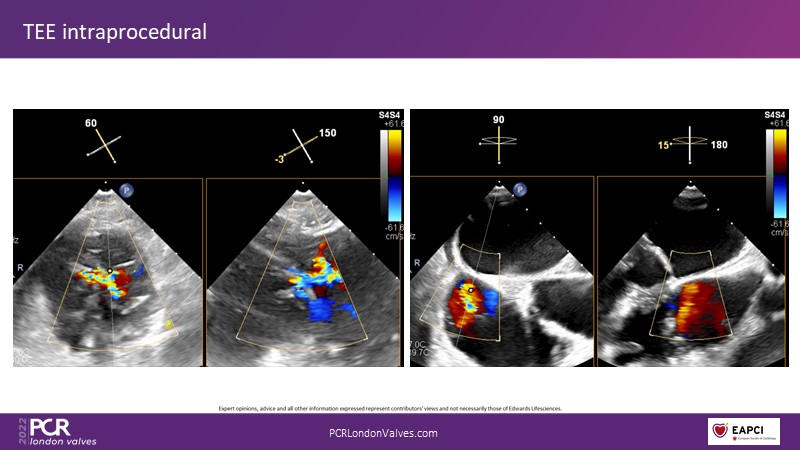

This innovative session takes you through the patient selection and anatomical characteristics when selecting amongst the different transcatheter options to treat tricuspid regurgitation, followed by a recorded demonstration using the PASCAL Precision repair system.